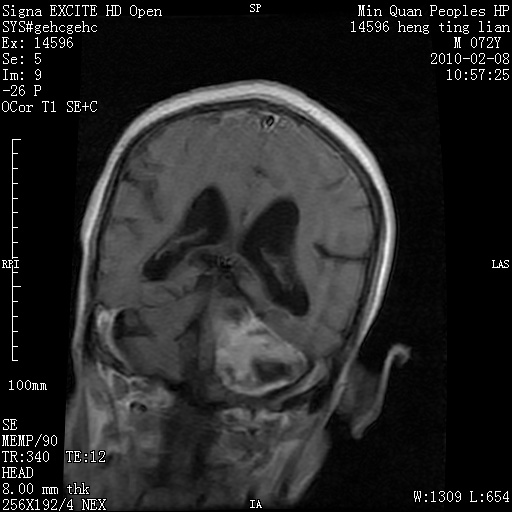

m,72,头疼,头晕两年,伴视力模糊三月,饮食呛咳两天。pe:颈部抵抗,左眼突出,左眼瞳孔约3mm,对光反射消失,双眼失明,伸舌困难,双肺呼吸音粗,心率110次/分,左上肢肌力i级,左下肢屈曲,肌张力高。现有08年2月19mri平扫及10年2月8日mri增强请会诊。ct病灶呈低密度伴散在点、片状等密度区,无明确钙化(无ct片资料可供上传)。[

脑外肿瘤,囊实性,环状不规则强化,内听道扩大,考虑神经源性肿瘤

左侧桥小脑区占位伴梗阻性脑积水----考虑 1神经鞘瘤 2室管膜瘤。

左侧桥小脑区神经鞘瘤伴梗阻性脑积水。

听神经瘤

左侧桥脑小脑角区肿瘤并脑积水,考虑听神经瘤,脑膜瘤?

左侧桥脑小脑角区肿瘤并脑积水,考虑听神经瘤,